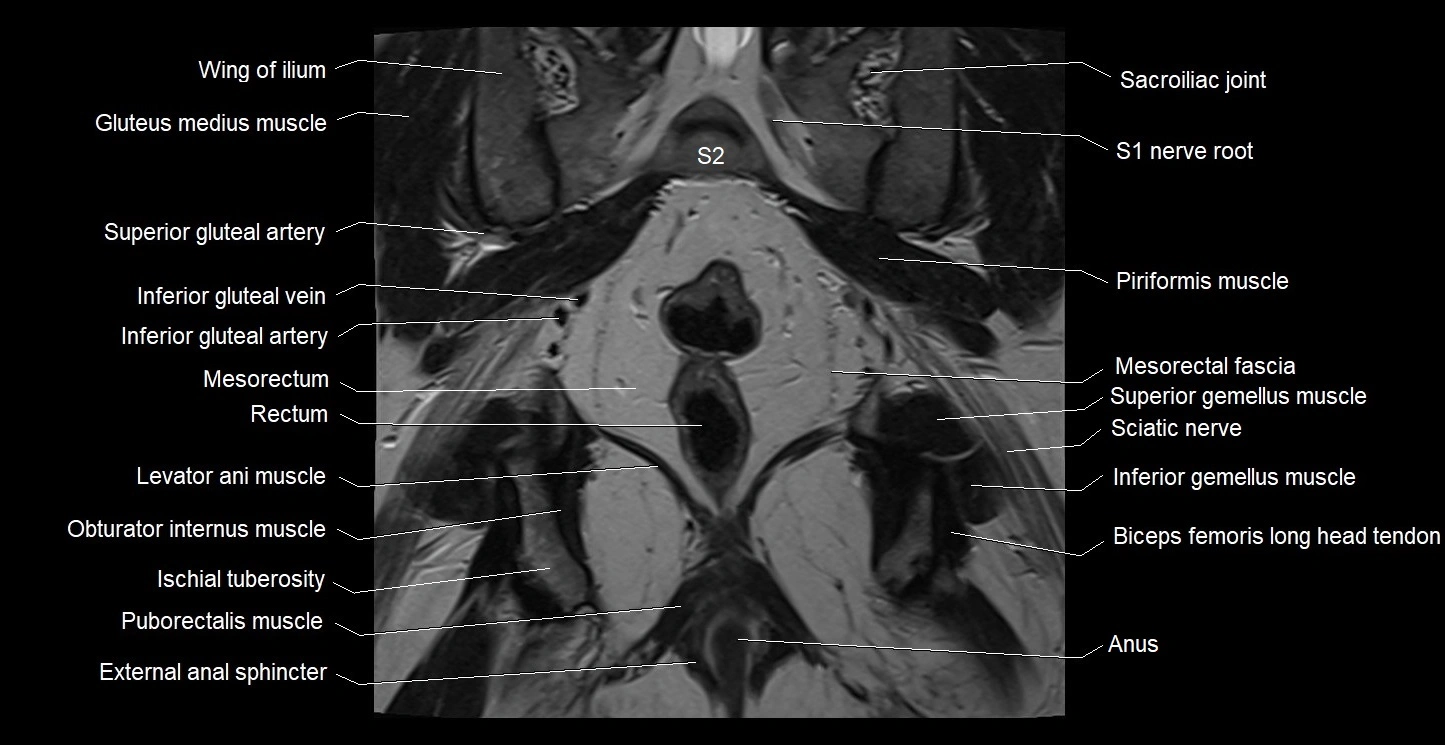

- External anal sphincter

- Gluteus maximus muscle

- Gluteus medius muscle

- Iliococcygeus muscle

- Inferior gemellus muscle

- Inferior gluteal artery

- Inferior gluteal vein

- Ischial tuberosity

- Levator ani muscle

- Mesorectal fascia

- Mesorectum

- Obturator internus muscle

- Piriformis muscle

- Puborectalis muscle

- Rectum

- Sacroiliac joint

- Sciatic nerve

- Spinal nerve S1

- Spinal nerve S2

- Superior gemellus muscle

- Superior gluteal artery